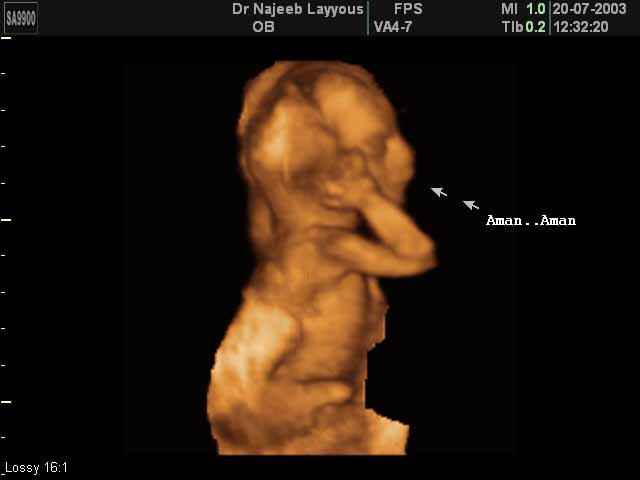

- Fetal Behavior Ultrasound Photos

- Fetal behavior during pregnancy

- Start Your Baby's Photo Album

- The importance of 4D ultrasound imaging in pregnancy

Ultrasound Photos in 3D showing Fetal Behavior Inside the uterus | Dr N Layyous